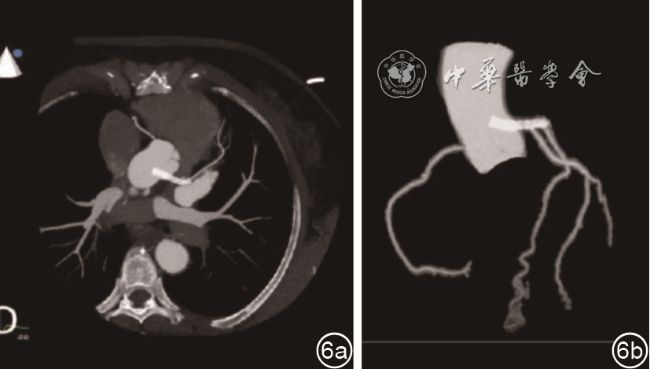

考虑患者曾行PCI手术,因此推测超声显示的双线状强回声可能是移位的冠状动脉支架。冠状动脉CT血管造影亦证实了超声心动图的诊断,CT检查见左冠状动脉内支架呈高密度结构,由左冠状动脉内突入主动脉根部管腔内,支架管腔通畅,未见狭窄及充盈缺损,前降支各段管腔偏细(图6)。

图6 冠状动脉CT血管造影检查示左冠状动脉内支架部分突入主动脉根部管腔内,前降支各段管腔偏细(图a为左冠状动脉主干层面成像;图b为冠状动脉CT三维重建图像)